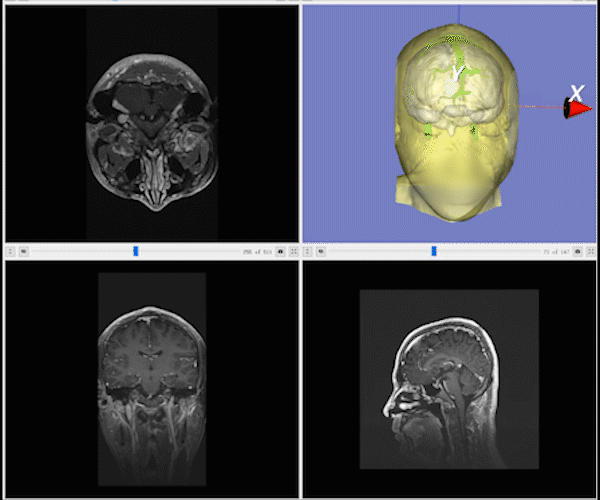

手术导航术中使用场景&系统核心组件

北京协和神经外科教研室主任、博士生导师王任直教授表示:“神经外科医生在手术时,不仅对病变定位精度要求高,同时还需要了解病变与周围血管和神经的关系,避免手术当中损伤这些重要的组织。过去我们只是凭着经验,将病人的CT或磁共振二维影像片子重新整合在大脑中形成三维图像。实际上,这个学习过程是非常漫长的,需要大量长期的经验积累。我们和腾讯共同研发的手术导航简单、方便、易用,可以帮助临床医生解决许多实际问题。”

为解决这些问题,基于腾讯AI Lab的前沿算法能力和协和医院的临床经验,腾讯自研发布了具有高精度、易操作、便携、低成本等特性的手术导航系统。以前需要专用的导航设备现在只需要一块普通的平板即可替代,新型导航在具有较高精度的前提下,将其成本压缩到传统手术导航产品的十分之一,填补了国内市场的空白的同时,也完成了手术导航系统的国产化替代。

基于腾讯 AI Lab 的前沿算法能力和北京协和医院神经外科多年的临床积累,国产手术导航系统能在术前、术中等多个环节,辅助医生提升诊疗效率。腾讯表示,目前这套系统已在北京协和医院神经外科开展了三十余临床试验,病例涉及脑出血、垂体腺瘤、胶质瘤、脑膜瘤、颅咽管瘤等多种疾病,与显微镜、内镜等器械配合应用,成功完成了各类手术。